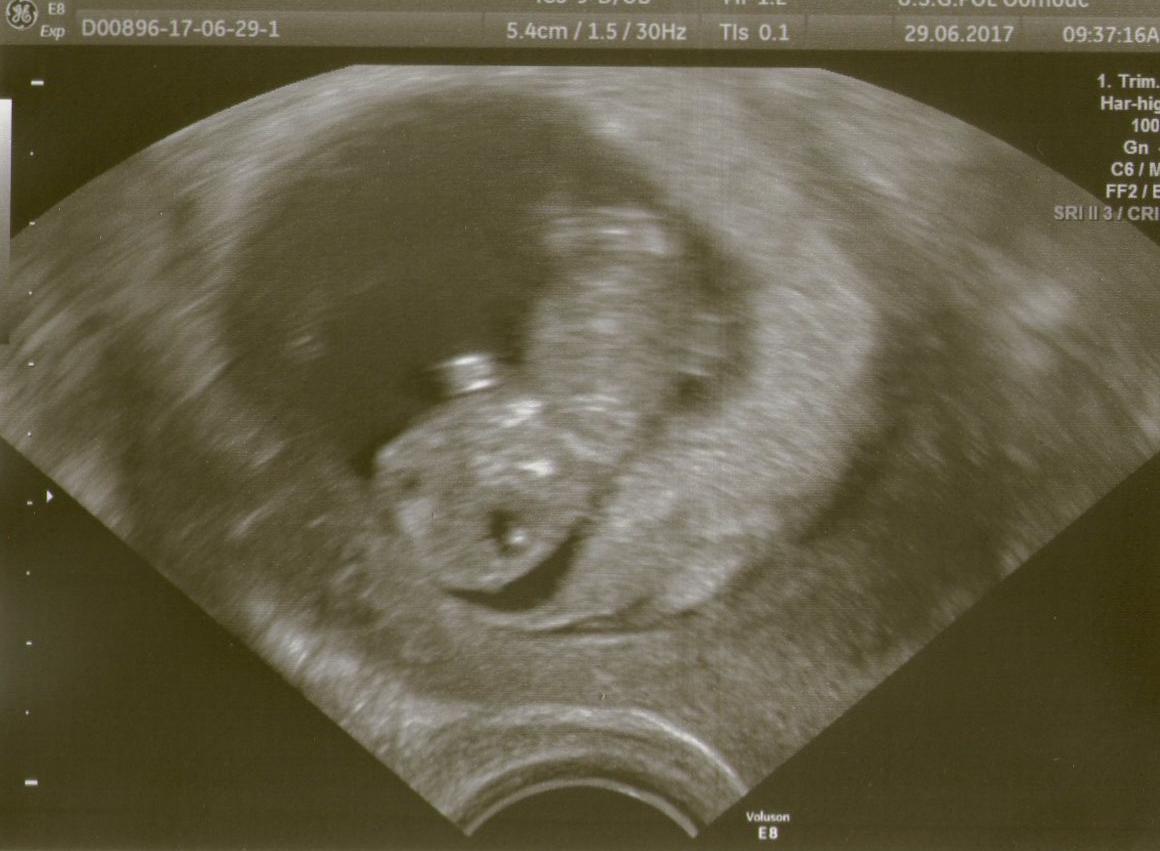

Ahoj holky,dnesni kontrola dopadla dobre.Merime 3cm,podle ultrazvuku dneska jsme 10+0tt a termin porodu se nam posunul z 30.1.2018 na 25.1.2018.Tyden nam odpovida podle MS.Dostala jsem tehu prukazku kde mi doktorka napsala termin porodu 2017 ale ja si toho vsimla az doma tak jsem si to prepsala ze 7 na 8.Dneska jsem dostala plno brozurek a plno terminu a do toho jsem se jeste dozvedela od mamky,ze vcera mela babicka pohreb,ze mi to nechtela vcera volat ze vi ze jsem tehotna.Ze zemrela minuly tyden ve spanku.Takze dobre i spatne zpravy.V pondeli 10.7.na lacno na krev,donest moc.Ve stredu 19.7.jdeme na 1 screening a pak v pondeli 31.7.na kontrolu.Doktorka mi rekla ze si mam zajit k obvodni doktorce a zubarce,nevim teda kdy,to mi nerekla kdy se tam tak chodi nebo do kdy.

@destovakapka mrzí mě odchod babičky,sle i já to tak měla,umřel mi děda 14dní před narozením Terezky. Jinak gratuluju k dobrým zprávám a krásné fotečce.

Ahoj holky, rada bych se mezi vas pridala 🙂 sleduju vas od pocatku. Pokud muzu. Az nyni mam potvrzene tehu ultrazvukem. Dnes jsem mela 1.kontrolu, podle MS jsem 6+1, ale dne UZ dnes nejak 5+ par dni, ale termin se stanovi na dalsi kontrole za 3 tydny, ted jsou pry ty odhady jste nepresne podle mereni. Srdicka pry uz byl naznak, ze zacina bit, kdyz bych pry prisla za 3 dny, uz by srdicko bylo krasne videt, jak pravidelne blika. Tak mam radost.

Ahoj holky,sleduji vás od začátku,tak bych se přidala k vám 🙂 Dnes jsem byla na druhém utz,pro potvrzení srdíčka...minule před týdnem nebylo vidět,dnes už krásně...jsem 7+0

Jsem přesně 9+5tt a mládě má 2,9 cm což jsem měřila na pravítku a už je to docela dlouhán. Dostala jsem k tomu i brožurky a časopis Betynka s mini dudlíčkem 😍 Nabízel mi neschopenku, pracuju v zemědělství u zvířat, ale zatim ji odmítám, aspoň do těch testů. Jsem asi pověrčivá, držíme to v tajnosti.

@evelin1251 Blahoželám. Pekný dlháň. Ja som bola v 8 + 5tt a mal 1,56cm 🙂